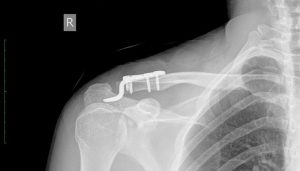

Акромиальный конец ключицы

Повреждение плечевого конца ключицы — очень частая травма, возникающая в результате падения или неудобного движения во время тренировки. Ключица — одна из относительно незащищенных и хрупких костей в человеческом теле, и для ее повреждения или вывиха не требуется больших усилий. Классификация и причины возникновения Гиппократ уже описал травмы плеча и различал внешний (акромиальный) и внутренний …